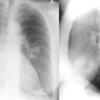

Asthma  PA& Lat

Date: 06/06/2004

Views: 5229